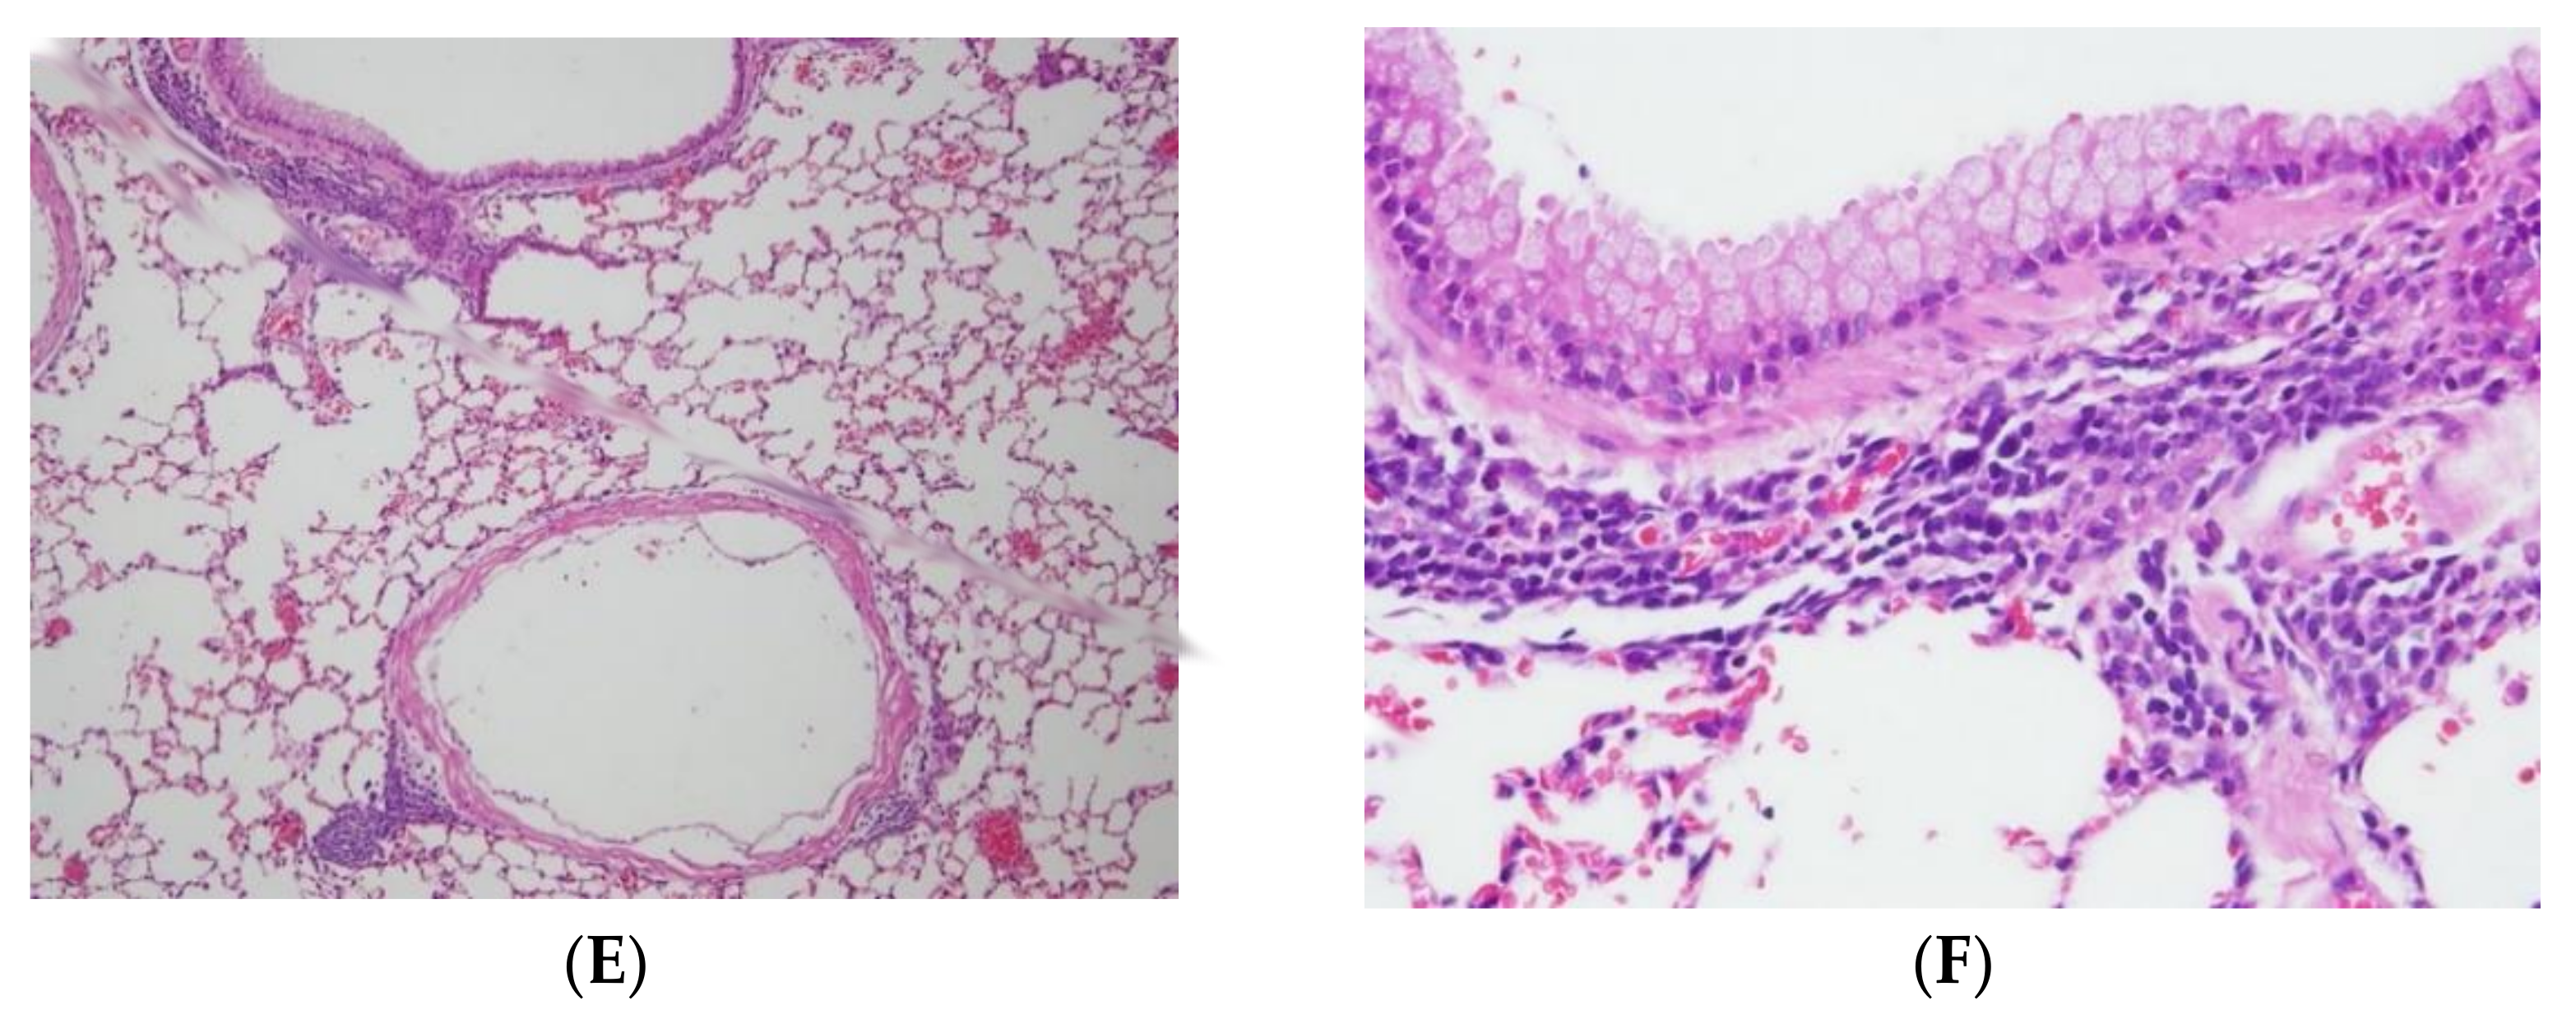

To evaluate the overall effects of menthone inhalation on the lungs of the experiment mice, the histology of the lungs stained with H&E (Figure 2 and Figure 3) and PAS dyes (Figures S1 and S2) was further studied. Histopathological findings of the lungs were found in the OVA-induced bronchiolitis mice. Normal architectures of bronchioles of the lungs in a NSC mouse (Figure 2A,B), and OVA-induced lungs shown as focal inflammatory cell infiltration, mainly neutrophils, lymphocytes, and (fairly) eosinophils, around perivascular and peribronchial spaces, were, respectively, graded as slight (2) in the DC group (Figure 2C,D) and minimal (1) in the PC group (Figure 2E,F). Furthermore, lungs shown as focal inflammatory cell infiltration, mainly neutrophils. lymphocytes, and (fairly) eosinophils, around perivascular and peribronchial spaces, were, respectively, graded as slight (2) in the ML group (Figure 3A,B), MM group (Figure 3C,D), and minimal (1) in the MH group (Figure 3E,F). Based on the pathology–individual score of the lungs in the OVA-induced peribronchiolitis mice, menthone inhalation dose-dependently decreased the inflammatory cell infiltration into perivascular and peribronchial spaces in the lungs that might have alleviated allergic inflammation of the lungs and airways of the experiment mice (Table 4).

Figure 2. Histopathological findings of the lungs were found in the OVA-induced bronchiolitis mice. There were normal architectures of bronchioles of the lungs in a NSC mouse ((A,B), NCL3-2); OVA-induced lungs, shown as focal inflammatory cell infiltration, mainly neutrophils, lymphocytes, and (fairly) eosinophils, around perivascular and peribronchial spaces, which were, respectively, graded as slight (2) in the DC group ((C,D) DC3-1); and minimal (1) in the PC group ((E,F), PC3-3); H&E stain; 100 and 400×.